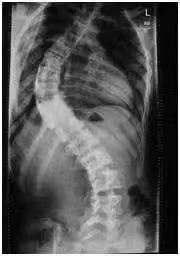

她的脊柱严重侧弯,特别是胸椎与腰椎部位,进行脊椎麻醉难度大。加之孕期无法拍片或核磁共振,无法准确判断脊椎的走向,因此在剖宫产时,麻醉医师都会建议进行全麻。

高女士脊椎弯曲度(参考图)